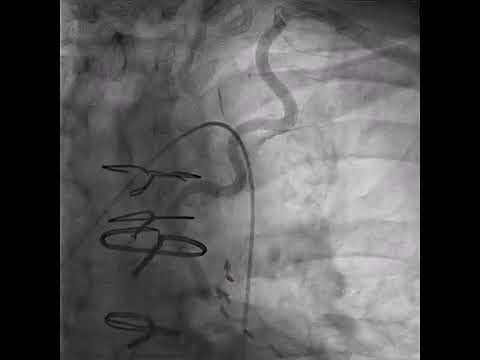

Hellow guys, Welcome to my website, and you are watching Carotid-Carotid Subclavian Bypass (Maham Rahimi, MD and Dong Lee, MD). and this vIdeo is uploaded by Houston Methodist DeBakey CV Education at 2019-05-21T09:24:07-07:00. We are pramote this video only for entertainment and educational perpose only. So, I hop you like our website.